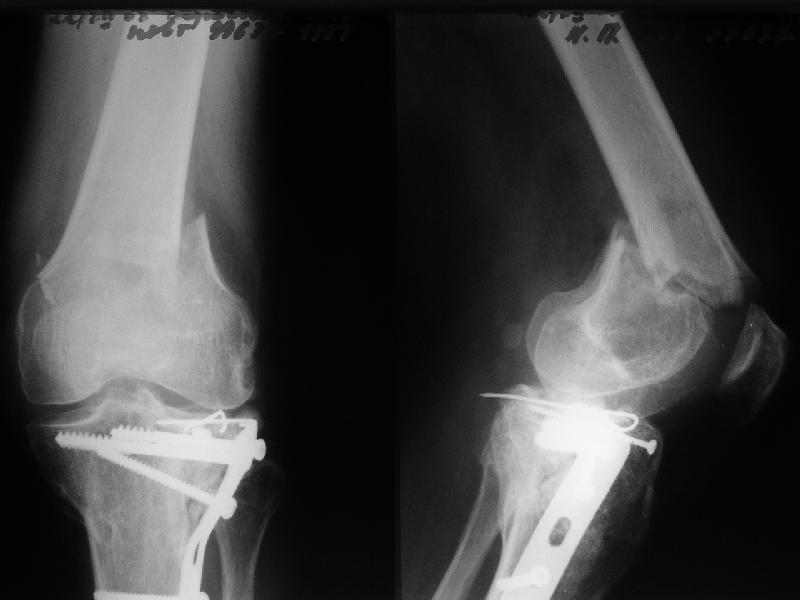

Мужчина 52 лет оперирован у нас 1,5 года назад по поводу перелома проксимального отдела большеберцовой кости. Все было неплохо, сгибал колено градусов до 60, ходил с полной нагрузкой, давно уже работал (служащий). Пару дней назад упал на скользкой улице - снимок в приложении. Какие предложения по лечению (пока первая мысль опять про закрытый интрамедуллярный остеосинтез)? И более широкий вопрос - как быть с локальным остеопорозом от бездействия после травм?

Merry Xmas!!! A male 52 years old was treated 1,5 years ago in our unit - ORIF of the proximal tibia. In 1 year follow-up all was OK - flexion 130, full WB, returned to work (white collar). Two days ago he fell on a slippery sidewalk - x-rays attached. How would you manage the injury? My first thought is closed nailing. And more common question - what we should do routinely with posttraumatic local osteoporosis? When full WB and function of the extremity is restored how long does a problem of such fractures exist?